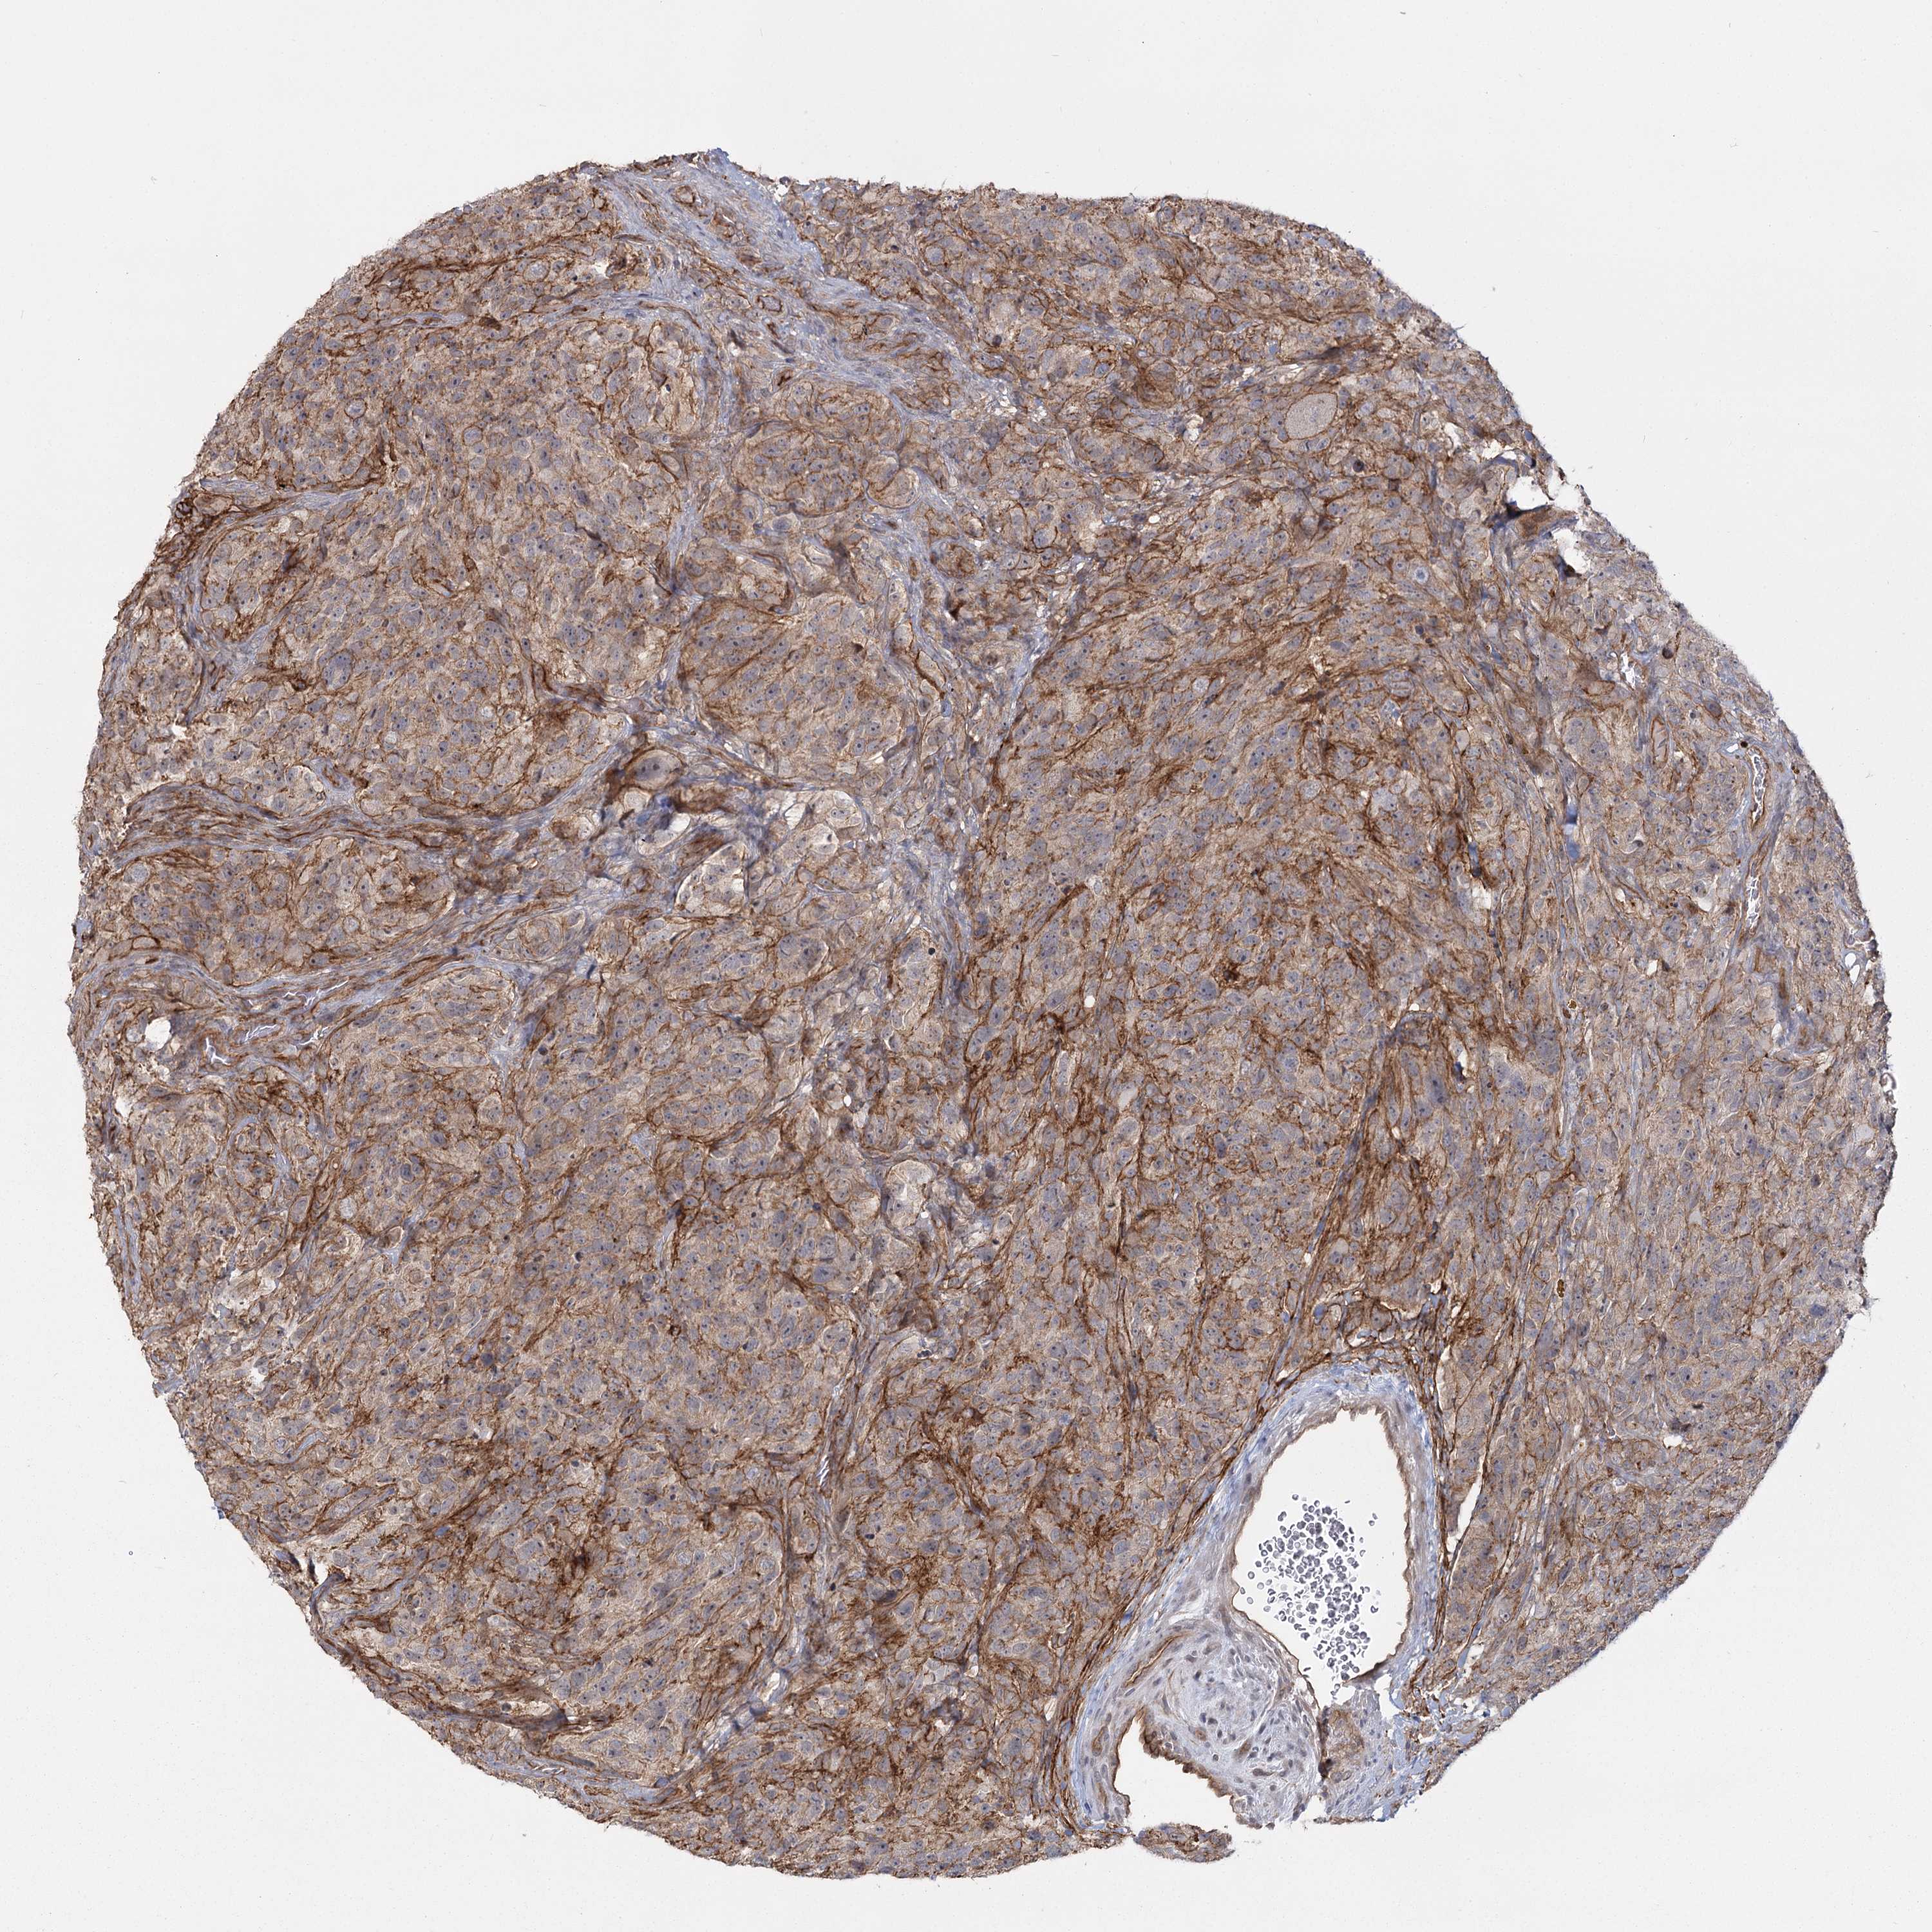

GLIOMA - Protein expressioni

A mouse-over function shows sample information and annotation data. Click on an image to view it in a full screen mode. Samples can be filtered based on level of antibody staining by selecting one or several of the following categories: high, medium, low and not detected. The assay and annotation is described here.

Note that samples used for immunohistochemistry by the Human Protein Atlas do not correspond to samples in the TCGA dataset.

Antibody stainingi

Antibody staining in the annotated cell types in the current human tissue is reported as not detected, low, medium, or high, based on conventional immunohistochemistry profiling in selected tissues. This score is based on the combination of the staining intensity and fraction of stained cells.

Each image is clickable and will lead to virtual microscopy that enables deeper exploration of all samples and also displays staining intensity scores, fraction scores and subcellular localization as well as patient and tissue information for each sample.

Antibody HPA036194

Staining

High

Medium

Low

Not detected

Intensity

Strong

Moderate

Weak

Negative

Quantity

>75%

75%-25%

<25%

None

Location

Nuclear

Cytoplasmic/membranous

Cytoplasmic/membranous,nuclear

Glioma, malignant, High grade

Glioblastoma, NOS